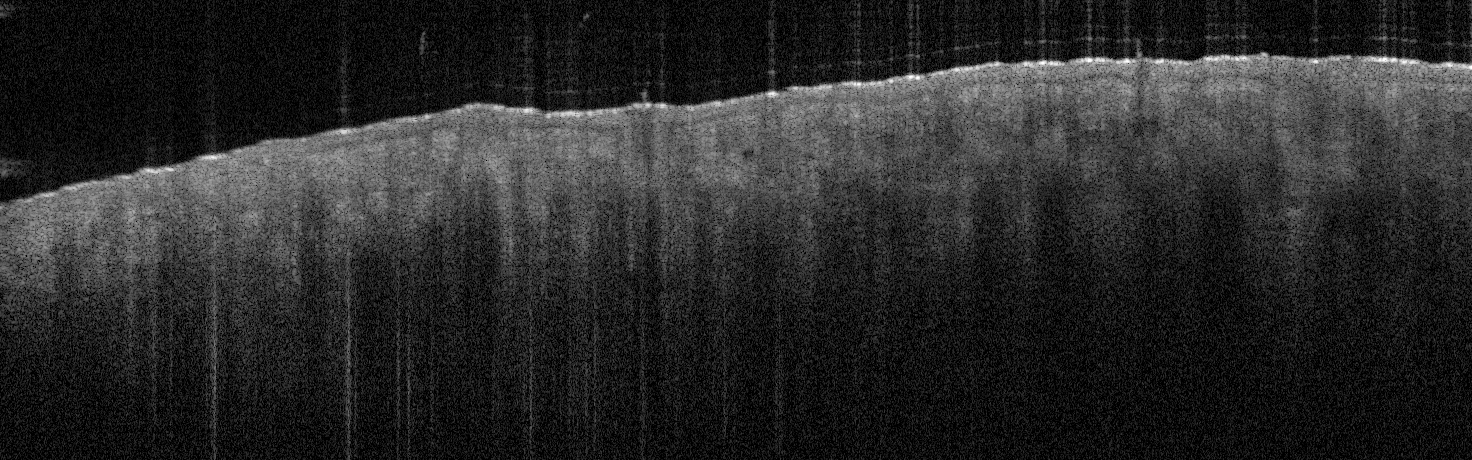

VA54: Left Superior Temple, Adjacent, Normal